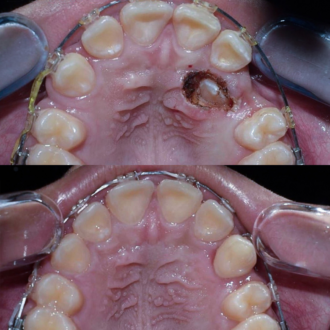

Во время диагностики обнаружен отлом фрагмента инструмента в корневом канале. Выполнено его безопасное извлечение, повторное перелечивание каналов, очистку и герметичное пломбирование.

Перелечивание с удалением двух переломанных инструментов. Пациент обратился с осложнением предварительного эндодонтического лечения. В каналах были обнаружены два переломанных инструмента. Выполнены их удаление и пломбирование каналов с соблюдением современных эндодонтических протоколов.